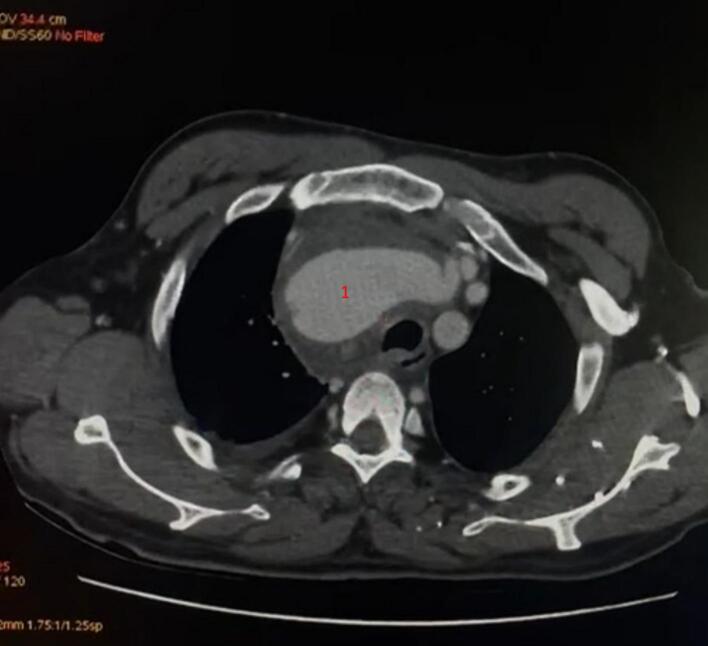

The CT scan confirmed the presence of a dilated aneurysm of the right subclavian artery starting 13 mm from its origin and extending to the cervical level, measuring a maximum diameter of 35 mm, with significant surrounding soft tissue inflammation, consistent with infection, but no signs of rupture. The lesion was closely associated with the brachial plexus and the subclavian vein, but no compression of these structures was evident. The CT scan also demonstrated a posterior aneurysmal fissure associated with a mediastinal hematoma and a small right-sided pleural effusion. Additionally, the scan revealed calcified mediastinal and hilar lymph nodes, which may have contributed to the vascular involvement by weakening the arterial wall through chronic inflammatory changes Fig. 1, Fig. 2.

Fig. 2.

Axial CT image showing the pseudoaneurysm of the right subclavian artery, with the mass effect on surrounding structures.